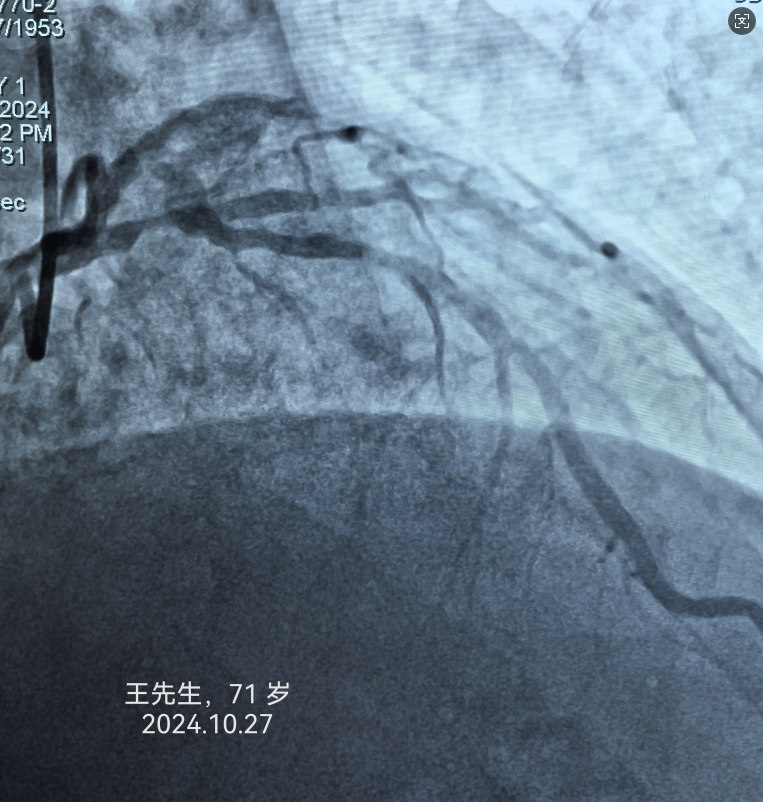

冠心病患者是猝死的高危人群。冠心病是中老年人最常见而且危害最大的心脏病之一,但随着生活节奏的加快和压力的增加,年轻人发病率也呈现增高的趋势。患者轻者可能无明显症状,但严重者可能会因此丧命。及时了解冠心病的早期症状对于早期发现和早期治疗有很大的帮助。